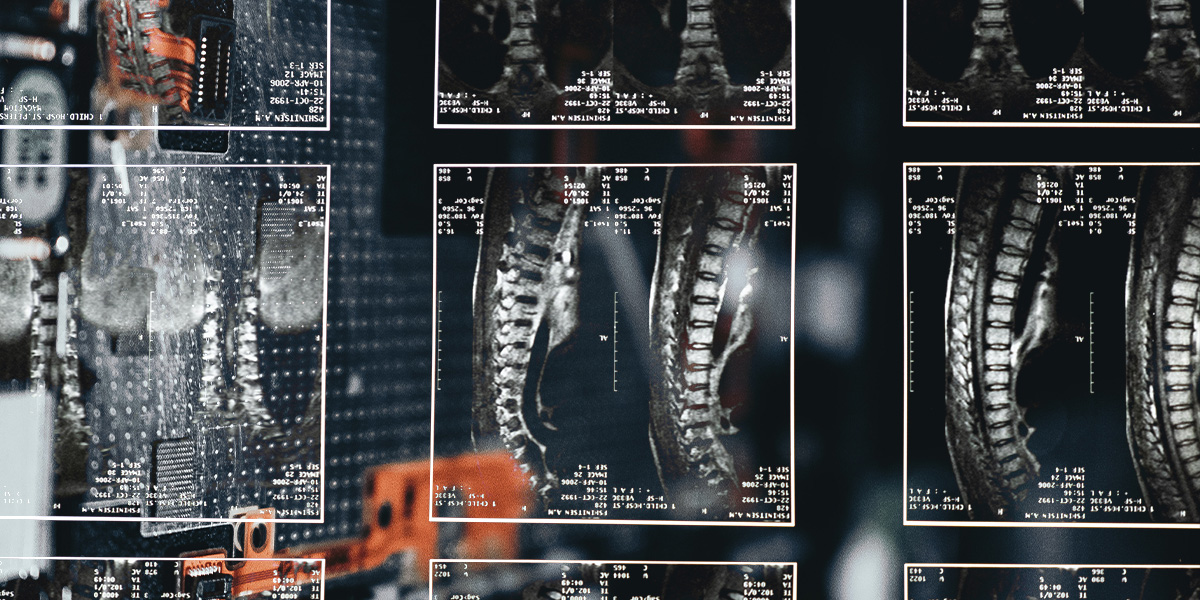

A gerincgyógyászati diagnosztikát segítő informatikai megoldást fejlesztettek az SZTE részvételével.

A gerincgyógyászati diagnosztikai folyamatot segítő informatikai megoldást dolgoztak ki a Szegedi Tudományegyetem (SZTE) kutatói a Budai Egészségközpont Kft.

Valamint a IFUA Horváth & Partners Kft. munkatársaival együttműködve - tájékoztatta a felsőoktatási intézmény közkapcsolati igazgatósága.

A szakemberek több tízezer gerinc MR-vizsgálat tudományos feldolgozásával olyan képi és szöveges információt is tartalmazó adatbázist hoztak létre, mely a mesterségesintelligencia-algoritmusok fejlesztésének és a gépi tanulásnak alapjául szolgál - ismertették.

Kitértek arra is, hogy a gerincről készített MR-felvételeket leletező alkalmazás felgyorsíthatja a kézi leletezést, valamint hozzájárulhat a pontosabb diagnózis felállításához.